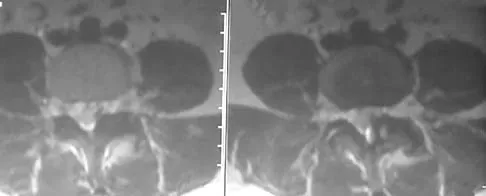

Question 40

A 30-year-old woman has pain in her right hand. The radiograph, CT scan, and biopsy specimen are seen in Figures 38a through 38c. What is the most likely diagnosis?

Explanation